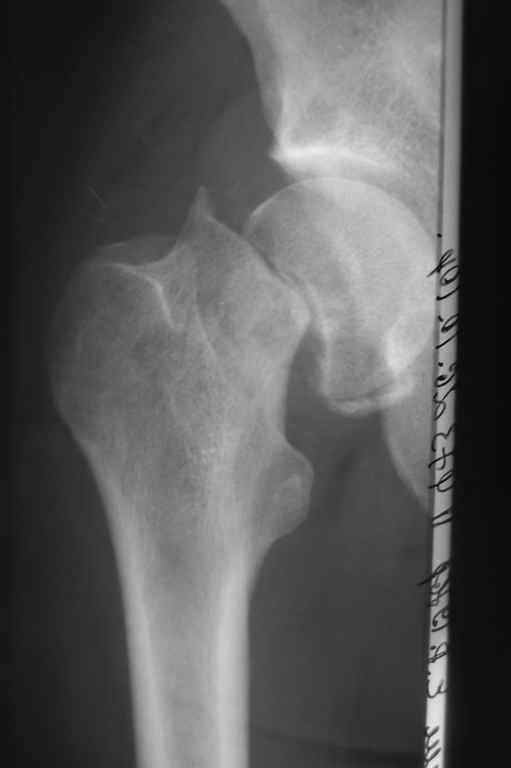

Застарелый перелом шейки бедра

Пациенту 34 года. Травма 10 недель назад.

Стоит ли попробовать выполнить остеосинтез, либо сразу - эндопротезирование?